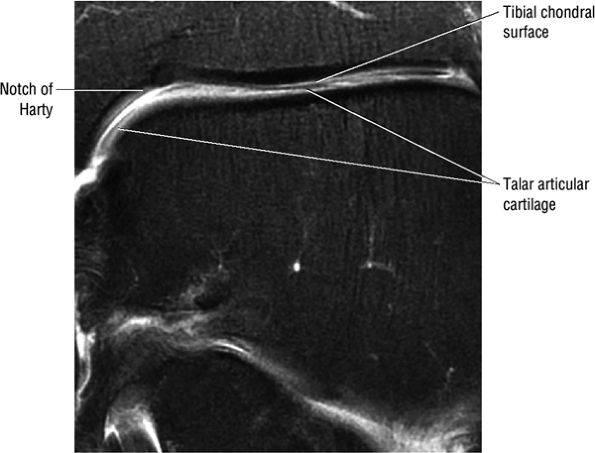

Decreasing the FOV or increasing the resolution in the coronal plane allows optimal separation of the distal tibial and talar dome chondral surfaces.

FIGURE 5.1 ● Visualization of tibiotalar articular surfaces using a coronal FS PD FSE sequence. Separation of the tibial and talar chondral surfaces is important in characterizing osteochondral lesions.